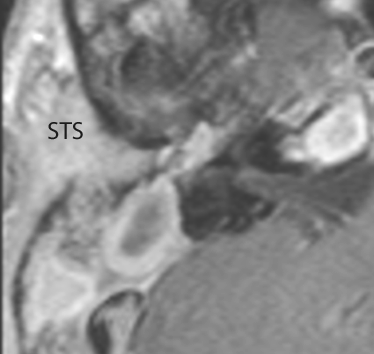

There is evidence of thrombosis, thrombophlebitis or other occlusive or inflammatory process of the sigmoid sinus, transverse sinus, the vein of Labbe’ or jugular bulb. [Yes/No]

There is evidence of thrombosis, thrombophlebitis or other occlusive or inflammatory process of jugular vein. [Yes/No]